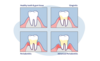

- Le bilan parodontal lors de la première séance, permet de connaitre la profondeur des poches infectées par sondage et radiologie. Cette profondeur détermine le degré de sévérité de la maladie.

- Un surfaçage des dents effectué au cabinet afin de désinfecter et de nettoyer sous révélateur de plaque les zones situées sous vos gencives. Il est complémentaire du détartrage. Procédé non chirurgical, il permet d’assainir la surface des racines dentaires et la gencive en profondeur. L’objectif est de désinfecter les tissus et de permettre la fermeture des poches parodontales, par une ré-adhésion de la gencive sur la surface de la dent. Lors de cette étape nous utilisons notre nouvel appareil de gestion parodontale de la marque EMS spécialement conçu pour un traitement optimal et indolore. Ultrasons - Poudre prophylaxique - Antiseptiques locaux sont utilisés. Des anesthésies locales peuvent être employées.

Parodontite et formation de la poche parodontale